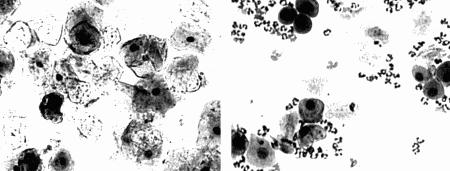

Фиг. 2.2.

Вагинальные выделения кошки (а). Выделения, типичные для фазы эструса. Большая часть клеток представляет собой безъядерные кератинизированные клетки или клетки с пикнотическим ядром. Присутствуют промежуточные клетки (b). Выделения, характерные для метэструса, — «течки», иногда наблюдаемой у кошек в конце эструса. Присутствуют поверхностные и промежуточные клетки, повышено содержание лейкоцитов. Этот короткий метэструс наблюдается в течение 24–48 часов (см. Приложение)